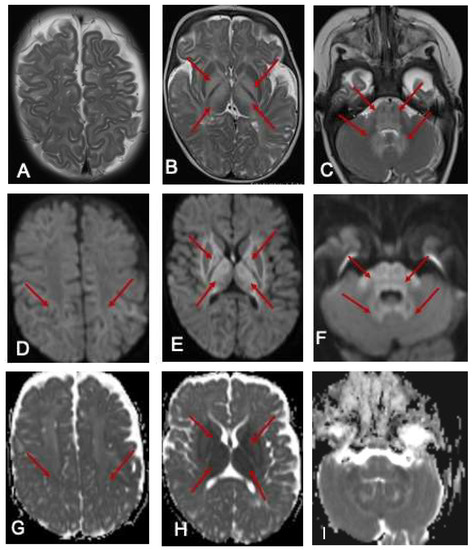

Our patient has improved significantly since her diagnosis and is now tracking along her developmental milestones. Formal assessments by her occupational and physiotherapists placed her within age-appropriate milestones at 15 months. Her communication skills were also age-appropriate at 14 months using the Rossetti Infant–Toddler language scale. She has had only one readmission aged 8 months for elevated BCAAs [leucine 859 μmol/L (RI 56–178), isoleucine 392 μmol/L (RI 34–106), valine 643 μmol/L (RI 108–314)], detected on routine dried blood-spot monitoring. She was otherwise clinically well and asymptomatic during this episode. At her last review, aged 2 years, her natural protein intake was 1.16 g/kg/day (14.5 g daily) with a RDI of 1.08/k/day, and BCAA free protein (MSUD Anamix Junior, Nutricia Australia) was 10 g daily. Her weight was just above the 55th percentile and height 75th percentile. Her two- to three-weekly DBS BCAA monitoring levels have remained normal for 8 months, with marginally elevated alloisoleucine (4–26 μmol/L, RI 0–3). Her repeat MRI at 10 months of age showed (Figure 2) complete resolution of the hyperintense signal changes and age-appropriate myelination.

Figure 2.

MRI of the brain 10 months later. The red arrow indicates the prominent perivascular spaces. From a follow-up MRI brain scan 10 months later, the T2-weighted axial images show significant improvement in myelination. Prominent perivascular spaces are also seen (A-arrow). There is resolution of the previously noted signal changes of basal ganglia and thalamus (B), and the brainstem and dentate nuclei (C).

Prognostication of clinical outcome may be difficult to determine in the acute decompensated state. Dramatic neuroimaging findings in the early stages may not correlate with eventual clinical outcomes [4], as demonstrated in our patient’s significant initial MRI abnormalities that were subsequently resolved with optimal dietary interventions and excellent compliance. This case further substantiates the reversibility of neurological insults sustained during acute decompensation, also reported in other patients where complete resolution of neuroimaging abnormalities has occurred concurrently with normalisation of BCAA levels [13].